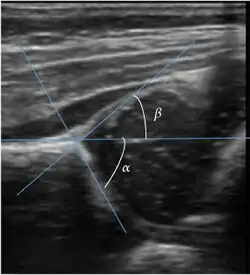

Ultrasound allows categorizing pediatric hips, according to Graf’s criteria, in four main types: normal, immature, and dysplastic (subluxed and dislocated). This classification is based on measurements of the acetabular inclination angle (alpha), cartilage roof angle (beta), and infant age. The femoral head coverage can also be determined by dividing the length of the femoral head covered by the acetabular fossa and the diameter of the femoral head. Its lower normal limits are 47% for boys and 44% for girls (Figure 11).[1]

Figure 11:

-

Useful ultrasound measures in neonatal hip sonography, alpha and beta angles.[1] -

Measurement of femoral head coverage.[1]